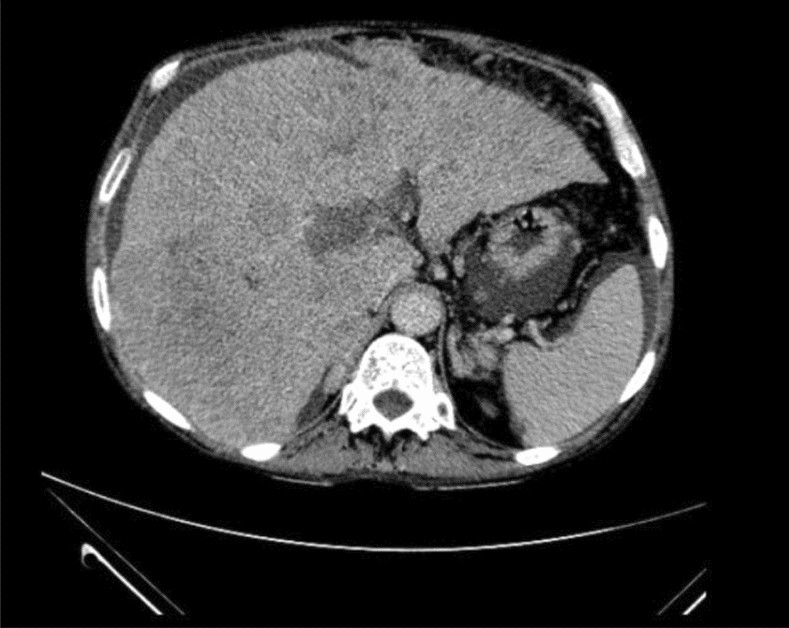

Figure 10

Example of a portal phase incorrectly classified as a delayed phase. Note that there is an infiltrative hepatocellular carcinoma with extensive portal vein thrombosis.